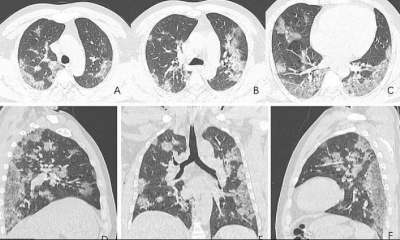

Corona Virüsle İlgili Korkunç Gerçek Ölen Hastanın Röntgeni Sayesinde Ortaya Çıktı

Dünyayı tehdit eden corona virüs neredeyse tüm dünyaya yayıldı